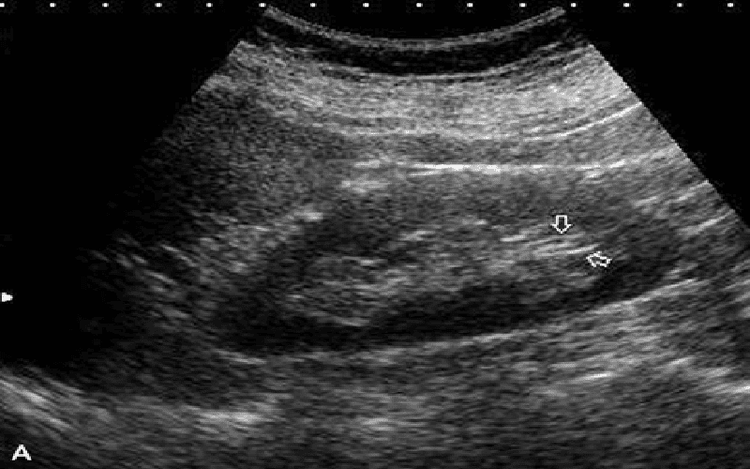

Siêu âm là phương pháp chẩn đoán hình ảnh có khả năng thăm dò tốt nhu mô thận và khoang quanh thận. Siêu âm Doppler còn giúp nghiên cứu rõ các mạch máu thận. Khi siêu âm, bệnh nhân được đặt tư thế nằm ngửa, chếch 2 bên hoặc nghiêng, có thể nằm sấp. Sau đó, bác sĩ dùng đầu dò tần số 3.5-5 MHz. Đầu dò sẽ phát, thu sóng siêu âm phản hồi. Hình ảnh siêu âm là hình ảnh cắt lớp 2 chiều và đen trắng. Đầu dò được quét theo nhiều hướng khác nhau, dọc thận, ngang thận và bàng quang.

Hình ảnh siêu âm sẽ thấy thận gồm 2 vùng phân biệt rõ: Trung tâm thận là xoang thận, ngoại vi là nhu mô thận. Thận được bao quanh bởi bao thận (viền tăng âm). Xoang thận có hình tăng âm màu trắng do chứa mỡ, có các vách mạch máu và vách đài bể thận nên phản hồi âm nhiều. Khi bể thận có nước tiểu sẽ thấy một lớp dịch rỗng âm màu đen ở vùng tăng âm. nhu mô thận giảm âm có màu xám và phản hồi âm ít.

Hình ảnh siêu âm bệnh xốp thận: Phần tủy thận có echo dày với những điểm có echo và một số có bóng lưng. Phương pháp siêu âm có thể phân biệt bệnh xốp thận với hoại tử gai thận và thận đa nang. Cụ thể, với hoại tử gai thận, siêu âm sẽ thấy có gai lột và calyceal ring sign.

Ưu điểm của kỹ thuật siêu âm thận là đơn giản, dễ thực hiện, có chi phí thấp, hiệu quả đánh giá chính xác, có thể thực hiện ngay tại giường bệnh, có thể tái khám nhiều lần và không gây hại cho sức khỏe. Siêu âm cũng có thể xem được hình thái thận theo 3 chiều không gian, có thể thấy bàng quang, tiền liệt tuyến,…